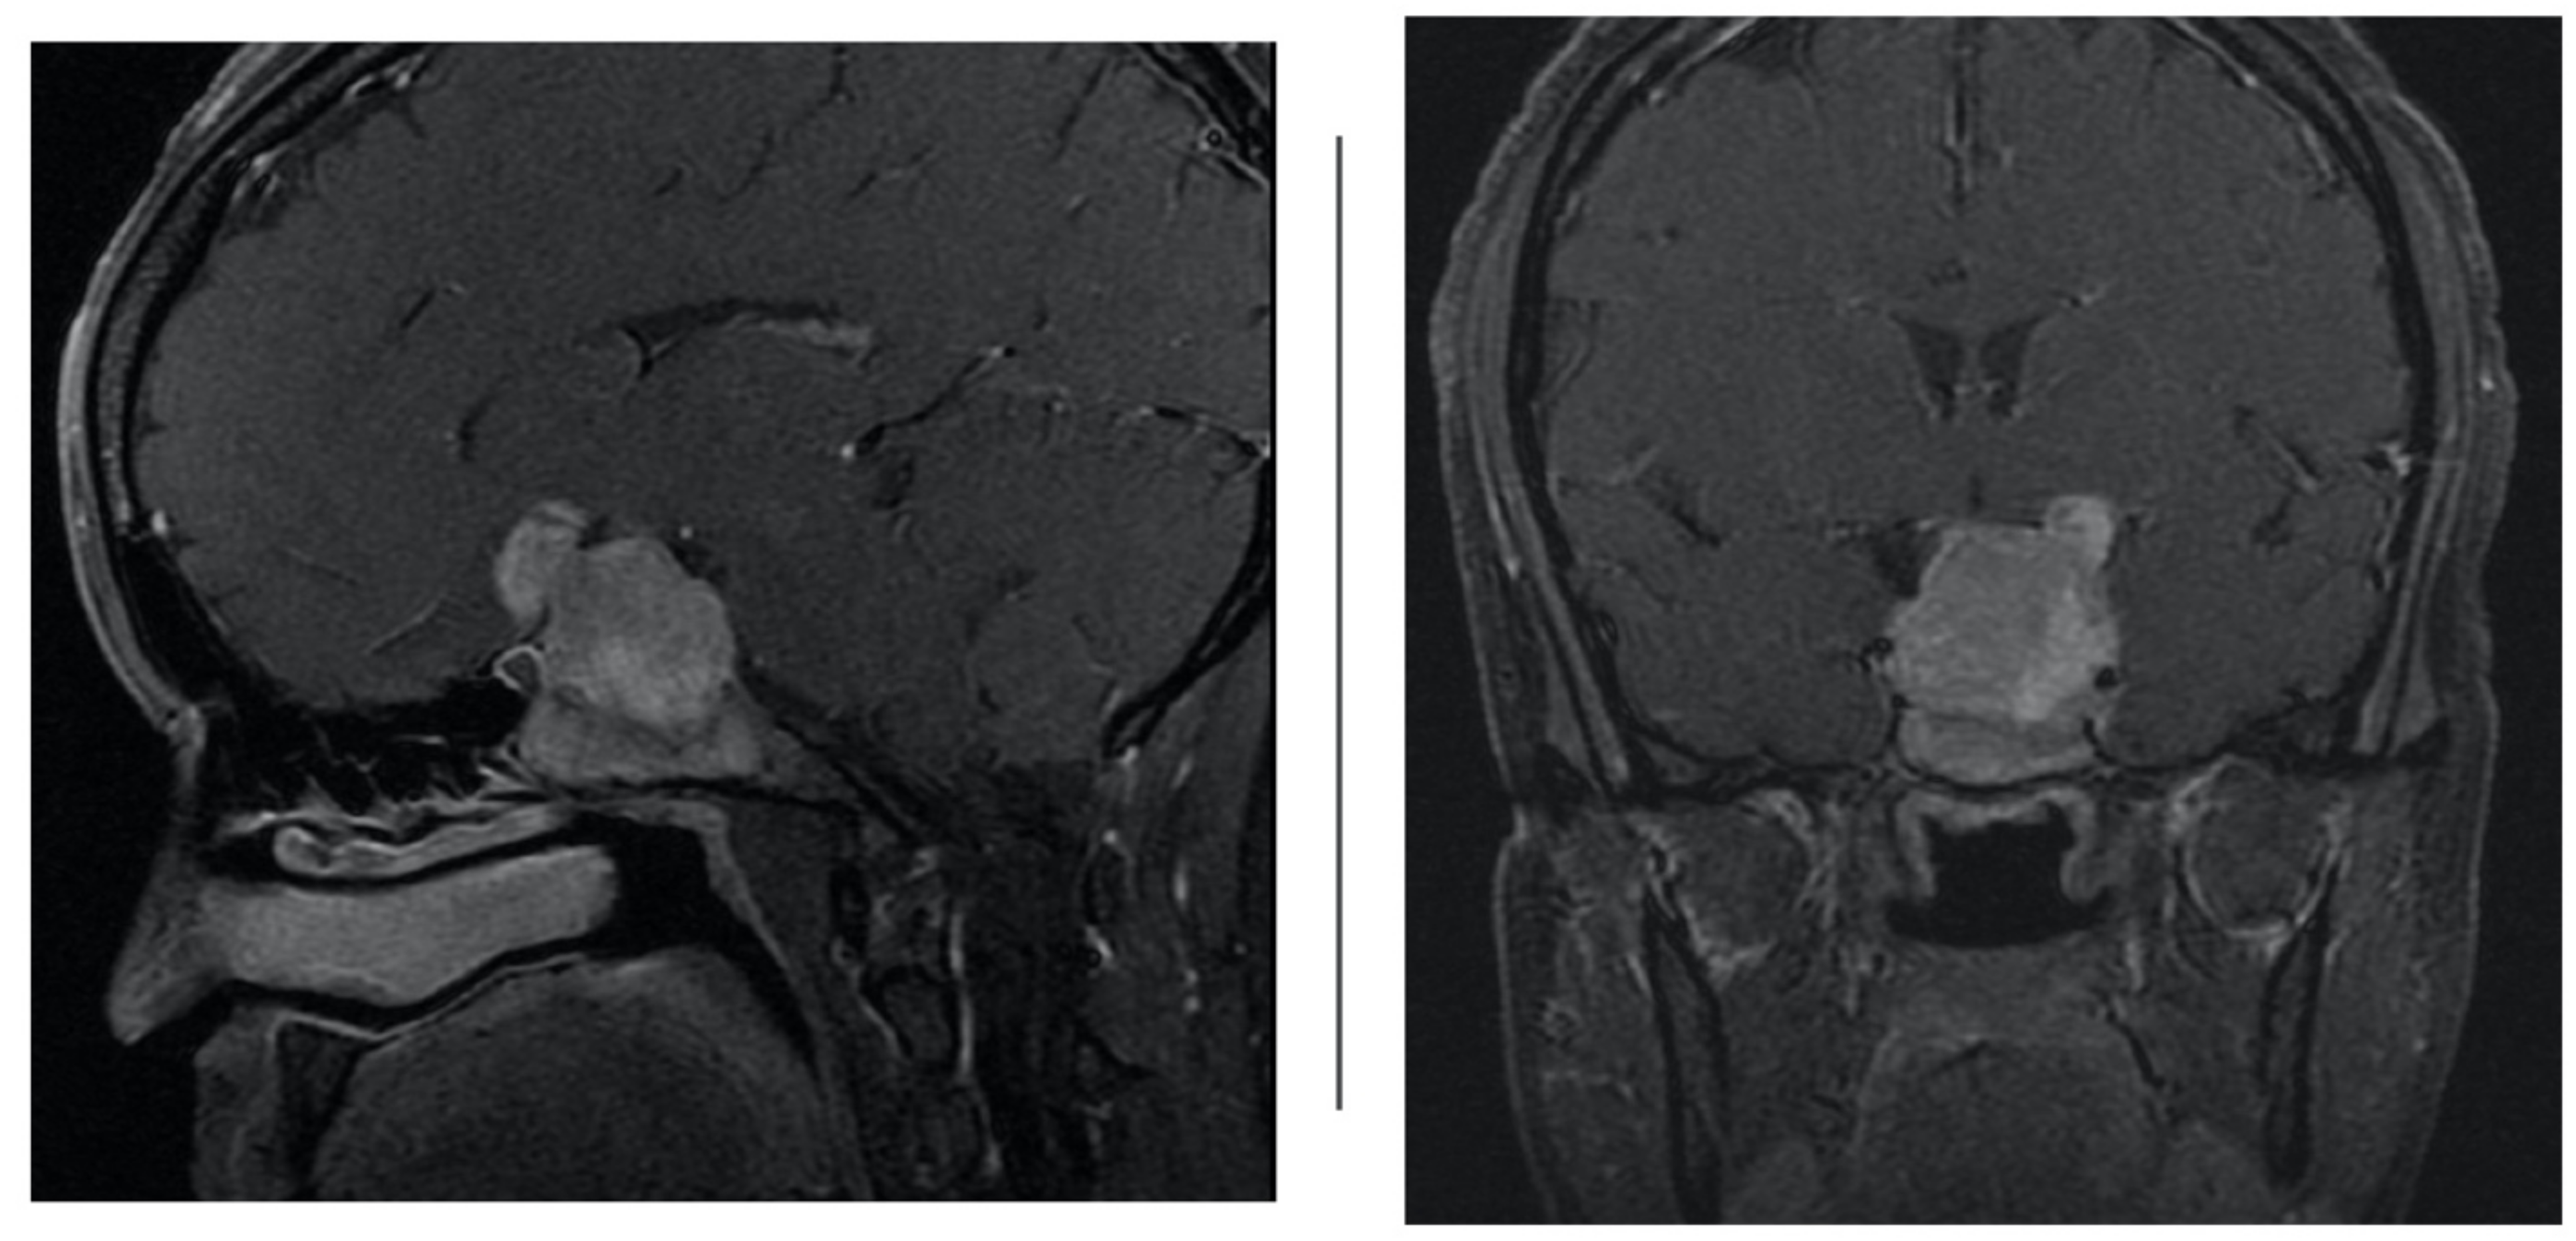

At our institution, four patients (n = 4) were assigned to acetazolamide therapy after they developed iatrogenic cerebrospinal fluid leak from transsphenoidal surgery for tumor resection from June 2018 to June 2019 by the senior neurosurgeon. Table 1 shows a summary of patient demographics. Average age was 42.5 years and average BMI was 31.6 (range 26.5–36.4). All four tumors were greater than 10 millimeters in size and had suprasellar extension (Hardy 3); in three of the four cases, the tumor compressed the optic chiasm and infiltrated the sphenoid sinus (Hardy 4). Further, in all four cases, the macroadenoma extended to or beyond the lateral aspects of the internal carotid artery, and in some cases extended into the superior and inferior cavernous sinus (Figure 2) compartment (Grade 3B). Average tumor volume was 21.24 [3]. Using the CSF leak grading system described by Esposito et al., all four patients had grade one to two CSF leaks, intra-operatively [8]. These leaks were repaired with a combination of dehydrated amniotic membrane, acellular dermis, and free mucosal flap based on the intraoperative judgement of the senior otolaryngologist.

Figure 2.

Sagittal and coronal T1 contrast-enhanced weighted magnetic resonance imaging (MRI) demonstrating large sellar and suprasellar pituitary macroadenoma extending into the cavernous sinus.